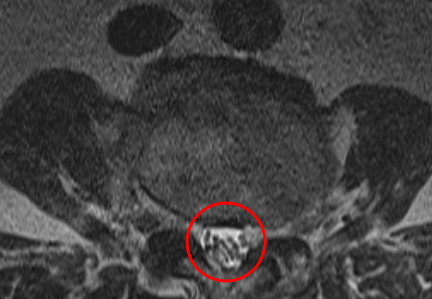

治療後

腰痛や、左臀部下肢外側の痛みと痺れの根本原因であるL3/4の狭窄を取り除く手術「PEL」を施し、神経の圧迫を取り除きました。またこの手術と同時に神経細胞の修復作用効果を期待して、濃縮血小板由来の成長因子を患部に注入する再生医療「PRP療法」を行いました。

術後の翌日には痺れが軽減。痛みは左のふくらはぎに少し残っているとのことでした。1か月後の定期健診では、左のふくらはぎの疼痛も軽減傾向に。手術前よりも腰痛は10から3に、左下肢疼痛は10から1に緩和しました。